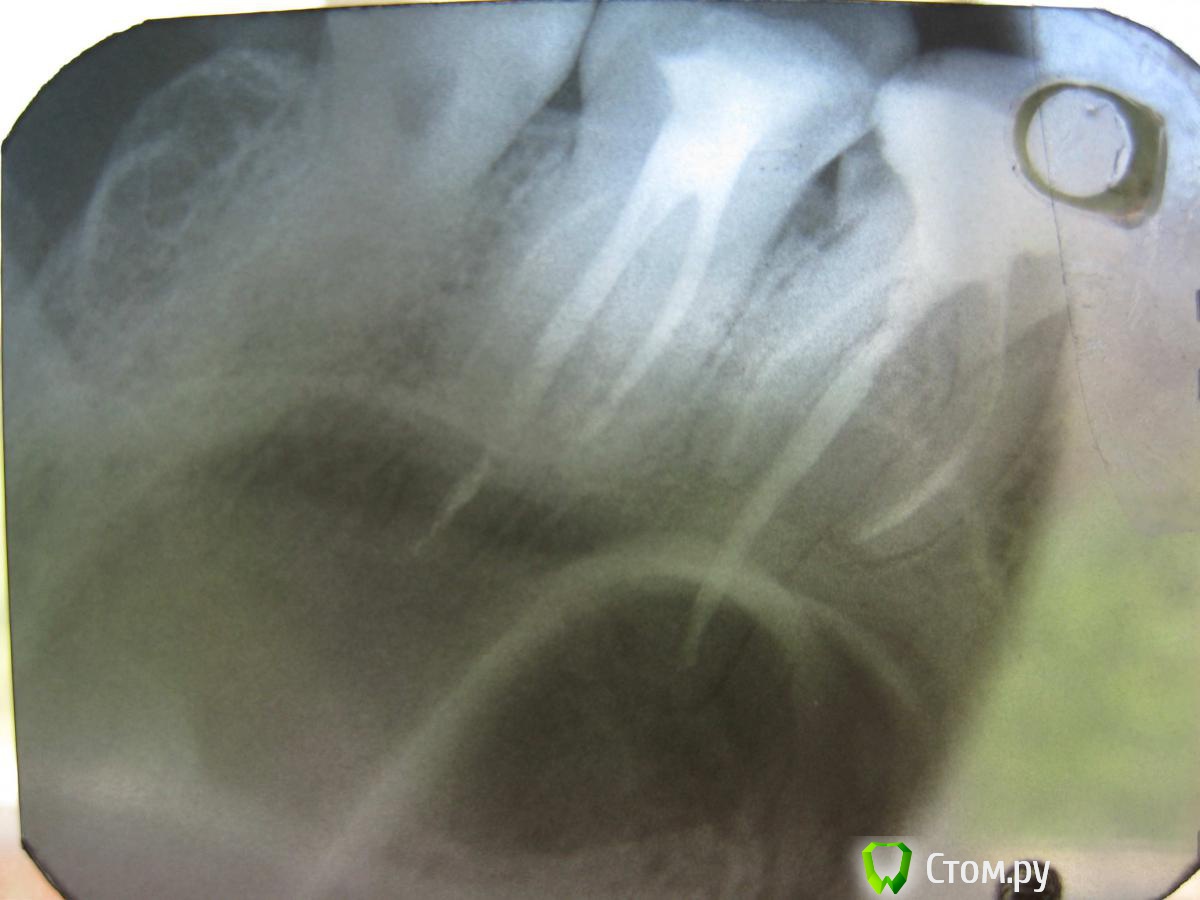

KateDav Опубликовано 18 июля, 2014 Автор Поделиться Опубликовано 18 июля, 2014 Вот прошел месяц и 5 часов мучений и похоже все стало еще хуже.Кажется мне пробили корень.Верхняя шестерка.Поясните пжлста, очень жду ваших комментариев. Ссылка на комментарий

red_butler Опубликовано 18 июля, 2014 Поделиться Опубликовано 18 июля, 2014 все хорошо Ссылка на комментарий

KateDav Опубликовано 18 июля, 2014 Автор Поделиться Опубликовано 18 июля, 2014 (изменено) все хорошоПравда?! А что это внизу, уходит за корень в бок ? плиззз поясните. Изменено 18 июля, 2014 пользователем KateDav Ссылка на комментарий

red_butler Опубликовано 18 июля, 2014 Поделиться Опубликовано 18 июля, 2014 Правда?! А что это внизу за корень в бок уходит? плиззз поясните. немножко силер за апекс вышел, это типа клея для гуттаперчи 1 Ссылка на комментарий

KateDav Опубликовано 18 июля, 2014 Автор Поделиться Опубликовано 18 июля, 2014 немножко силер за апекс вышел, это типа клея для гуттаперчиТак значит пробили верхушку корня, раз он вытек, видно же что ЗА корень уходит. Ссылка на комментарий

red_butler Опубликовано 18 июля, 2014 Поделиться Опубликовано 18 июля, 2014 Так значит пробили верхушку корня, раз он вытек, видно же что ЗА корень уходит.нет, все нормально, в верхушках зубов есть отверстия, через которые входитят сосуды и нерв Ссылка на комментарий